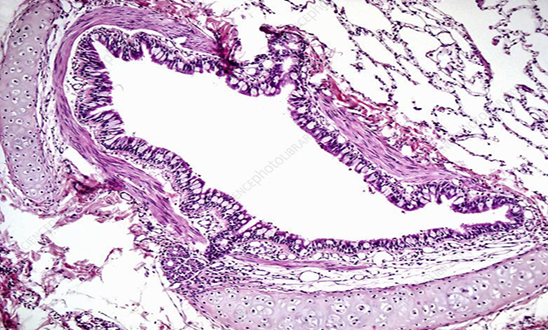

Trachea

(low power view)

Blue- Hyaline cartilage

Green- epithelium

Yellow- Glands in submucosa

(medium power view)

upper part: submucosa

lower part: cartilage

1. Epithelium

2. Tracheal glands in submucosa

3. Elastic membrane

4. Perichondrium

5. Hyaline cartilage

6. Trachialis muscle

7. Adventitia